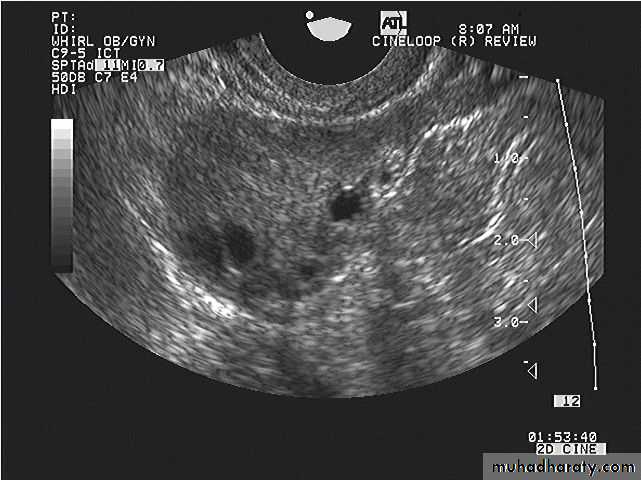

Images from women with differing expressions of the four major subtypes of the metabolic syndrome associated with polycystic ovary syndrome (A–D). The images exhibit quite differing ultrasonographic appearances in the size and distribution of follicles within PCOS ovaries. A recent corpus luteum is clearly visible in the ovary in panel (D).

Images from women with differing expressions of the four major subtypes of the metabolic syndrome associated with polycystic ovary syndrome (A–D). The images exhibit quite differing ultrasonographic appearances in the size and distribution of follicles within PCOS ovaries. A recent corpus luteum is clearly visible in the ovary in panel (D).• POLYCYSTIC OVARY SYNDROME